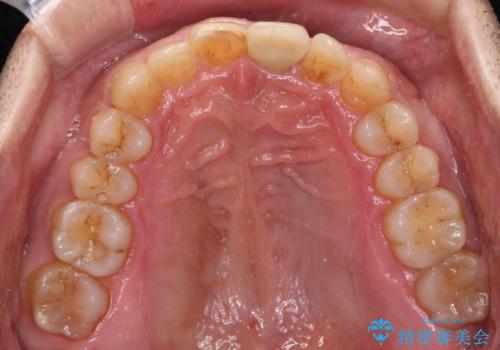

- 上下前歯のデコボコと下顎小臼歯の欠損によるスペースを気にして来院された患者様です。

下顎は左右1本ずつ小臼歯が欠損しており、右側にはやや大きな欠損がありました。

欠損により下顎歯列は相対的に小さく、上顎に深く咬みこんでしまうディープバイトとなっていました。

インビザラインによる治療を希望されたため、左側のスペースは閉じ、右側はスペースをより拡大し、インプラント補綴を行うこととしました。

咬合力が強く、インビザラインのみではディープバイトを改善することができず、半年間ほどワイヤー装置による矯正治療を行いました。

インプラントの埋入は矯正治療中に行い、矯正治療後はインプラント上補綴および、前歯のセラミック治療を行いました。